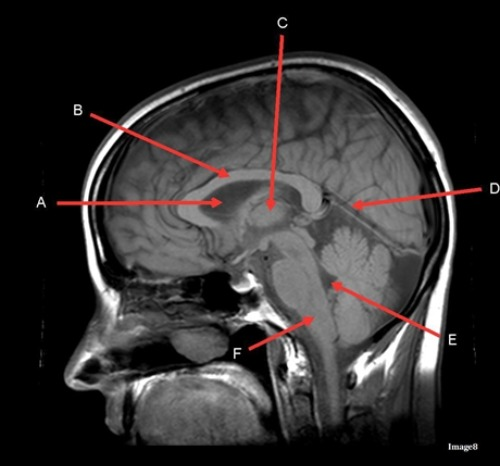

Letter C in image 8 is pointing to:

C. Thalamus

Letter D in Image 8 is pointing to:

A. Tentorium

Letter A in Image 8 is pointing to:

E. Lateral Ventricle

Image 8 is an example of a ____ weighted sequence acquired in the ____ scan plane.

B. T1; Sagittal

Letter B in Image 8 is pointing to:

B. Corpus callosum

Letter E in Image 8 is pointing to:

D. Fourth ventricle

Letter F in Image 8 is pointing to:

E. Medulla oblongata